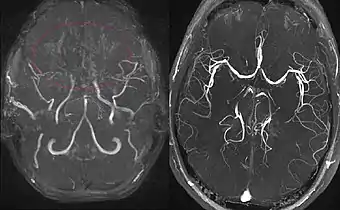

(derecha) Paciente sano, para comparación

El diagnóstico se basa en las técnicas de neuroimagen como la angiografía convencional o la angioresonancia, demostrándose la típica rete mirabile o microcolateralización. Además, existen microaneurismas asociados que pueden causar hemorragia pudiéndose detectar con estas técnicas. En la angiografía, para poder diagnosticar la enfermedad se deben observar los siguientes signos:[2]